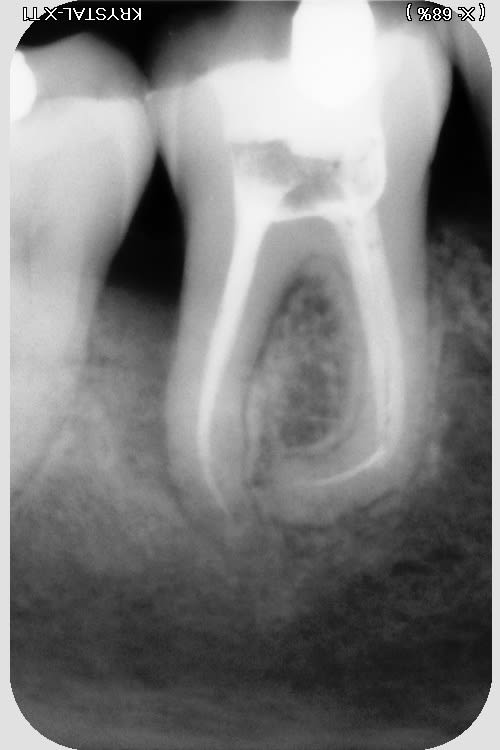

j'ai trouvé ça...rien de parfait malgré l'utilisation de broches manuelle, en alternance avec les rotatives sur certaines racine "légèrement coudées"....

pano et scan plus tard